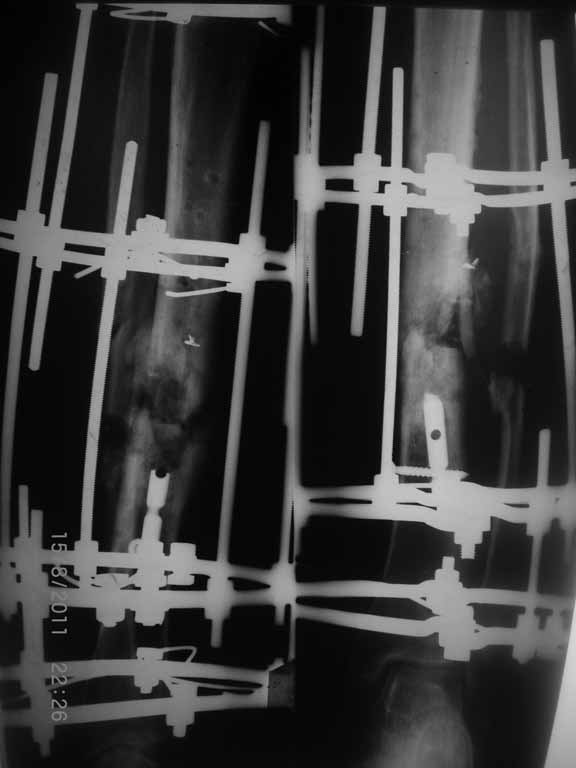

Как-то вот нет уже желания открываться в зоне ложного сустава. Мы бы

попытались сделать закрыто. Винт в дистальном отломке удалить через прокол.

Кусок гвоздя оставить. Новый гвоздь (солидный), возможно с покрытием.

Примерная ситуация. Пациент 37 лет. Синтезировали где-то пластинкой. Попал к нам через 2 месяца.

19 апреля убрали через проколы пластину с винтами, пересекли fibula, наложили аппарат.

Немного потянули по оси, убрали вальгус, ротацию. 22 апреля (на 3-е сутки) заштифтовали окончательно. 29 апреля выписали из отделения. На все ушло 10 дней.

С уважением, Никита Заднепровский